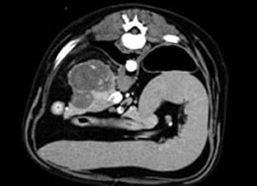

컴퓨터 단층촬영(CT) 검사

-

CT는 방사선 (X-선) 을 이용하여 인체의 미세한 조직을 컴퓨터가 선명한 단층영상 및 3차원 입체영상으로 재구성시켜 병변을 정확하게 진단하는 검사입니다. CT는 인체의 아주 작은 병변도 발견할 수 있는 최첨단 장비입니다.

대부분의 CT 검사에서는 병소의 윤곽이나 형태를 명료하게 나타나게 하기 위해서 정맥에 조영제를 사용하여 정확한 진단을 하게 합니다. 고성능의 컴퓨터를 이용한 3차원 입체영상으로 재구성하여 질환을 분석하여 검사의 정확한 정보를 제공하여 병변의 조기진단에 도움을 주며, 단 한번의 검사로 많은 정보를 얻을 수 있을 뿐만 아니라 여러 병변을 볼 수 있어 중복 검사의 시간 및 고통을 줄일 수 있습니다.